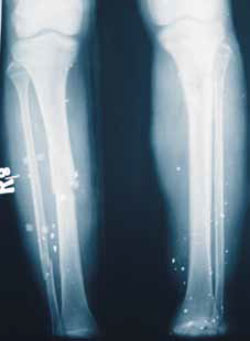

7. Тяжесть перелома: тяжесть некоторых травм неизбежно будет находиться где-то между баллами F1 и F2. Для простоты изложения этот вопрос в данной статье мы не будем подробно рассматривать - посвятим этому отдельную статью. Примером клинически незначимого раздробленного перелома (F1) является рана с раздробленной малоберцовой костью, но с незатронутой большой берцовой костью (рисунок 5).

Рисунок 5. Огнестрельное ранение: перелом F1 (клинически незначимый раздробленный перелом) малоберцовой кости